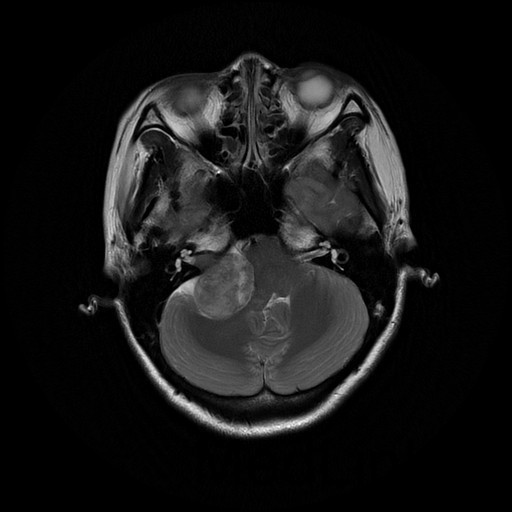

主诉:双眼视物模糊2月余 病史:中年女性,慢性病程。2月前无明显诱因出现双眼视物模糊,当地医院MRI提示:右侧桥小脑角处异常信号,占位,脑膜瘤?胶质瘤?血管母细胞瘤?建议增强扫描。

查体:神志清醒,查体合作。双眼视物模糊,眼球运动无明显异常。双侧瞳孔等大等圆,直径3mm,对光反射灵敏。 辅查:头部CT示:右侧桥小脑角区占位,考虑听神经瘤可能,并梗阻性脑积水。建议进一步MRI检查;头部MR示:右侧桥小脑角区占位,考虑为听神经瘤,并梗阻性脑积水;DTI示脑桥、桥臂及右侧桥小脑角白质纤维束受压移位。

随访:术后病理结果提示:(右侧桥小脑角处肿物)肿瘤由梭形细胞构成,可见疏区及密切,部分细胞呈栅栏状排列,细胞有异型性,核分裂可见,间质有散在淋巴细胞浸润,结合免疫组化结果,符合神经鞘瘤。 讨论:听神经瘤是桥小脑区最常见的肿瘤,也是最常见的脑神经瘤,绝大多数病理类型为神经鞘瘤。下面结合本例影像学习一下其影像表现:首先就是部位,发生于桥小脑区的占位第一反应是听神经瘤,而且和岩骨是呈锐角相交,该征象可以和发生于该部位脑膜瘤鉴别。另外,肿瘤沿听神经长如,导致内听道扩大也是一个重要征象。增强扫描可见明显强化,这可以和发生于该部位的胆脂瘤鉴别。